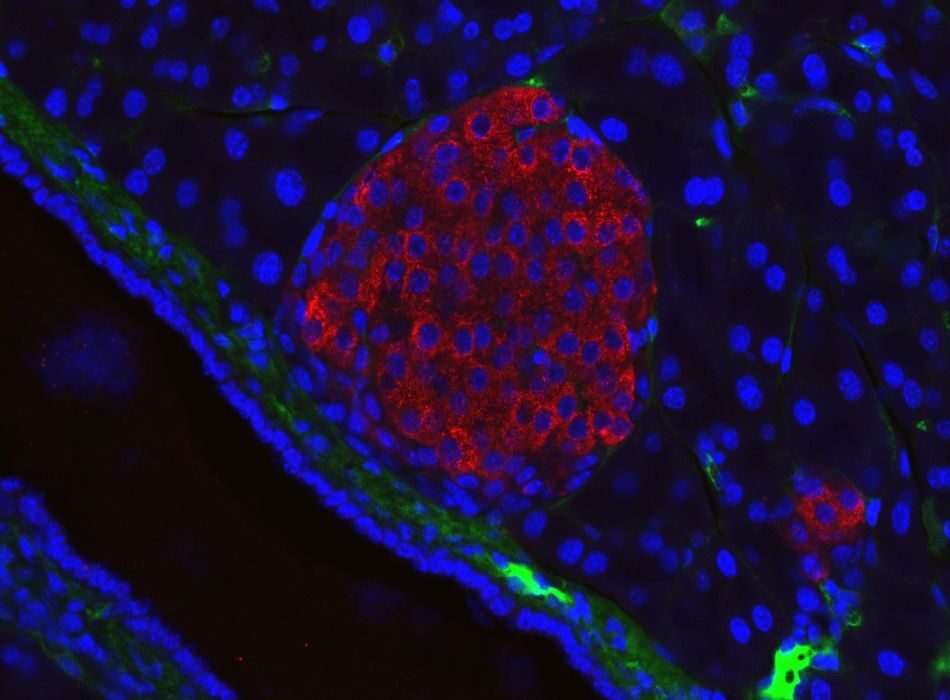

New Bioink Enables 3D Printing of Insulin-Producing Cells for Diabetes Therapy

A major breakthrough in bioprinting has occurred.